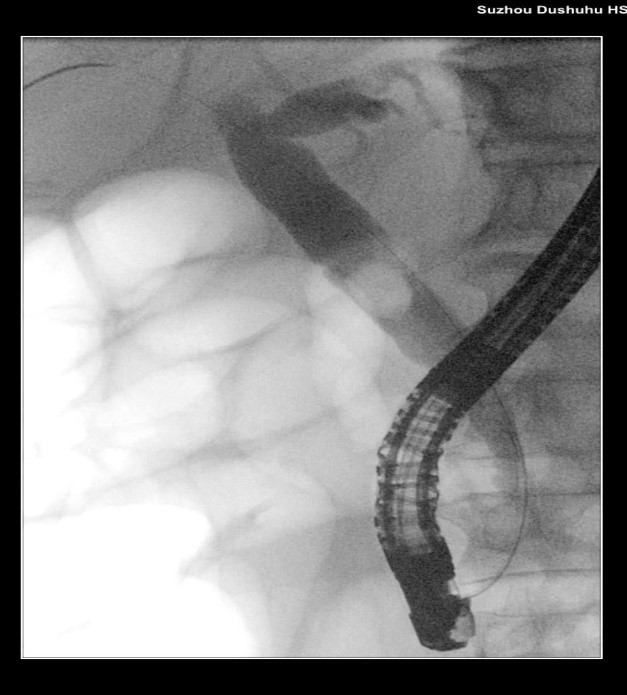

苏大附四院ERCP团队在手术中看到陈大爷的胆总管在结石的影响下已经宽达13mm,结石大小11*10mm,将十二指肠乳头切开并扩张后用取石球囊把结石取出,置入胆管支架使胆汁充分引流,顺利解除了胆道梗阻。

取石前